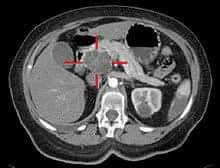

هل تعلم أن معظم حالات سرطان البنكرياس مازالت تكتشف متأخرة وهناك حالات كثيرة تكتشف متأخرة جدا ولذلك لتأخر المريض في الذهاب إلى الأطباء المتخصصين والكشف الطبي نظراً لموقع البنكرياس داخل البطن ونظراً لطبيعة هذا السرطان الخطير وهذا يؤدي إلى نتائج سيئة لهذا السرطان . والأمل يكمن في الإكتشاف المبكر لهذا السرطان الخطير وإجراء عملية إستئصال الورم السرطاني مبكراً والعلاج الكيماوي بعد العملية.

ولذلك فنحن ننصح المرضي بالذهاب إلى الطبيب مبكراً جداً عند بداية حدوث أي أعراض صفراء إنسدادية مثل تغير لون البول إلي الأصفر الداكن وبداية تغير بياض العين إلى اللون الأصفر، وكذلك عند ظهور مرض السكري، أو نقصان الوزن، وقد لا يكون هناك ألم بالبطن في حالات كثيرة، وقد يكون هناك ألم بالبطن أعلي منطقة السرة وخصوصاً عند حدوث تأخر في الذهاب إلى الأطباء المتخصصين للتشخيص والعلاج، وهناك أعراض أخري حسب مرحلة هذا السرطان .

ونحن نرجو من السادة الزملاء الأطباء المهتمين بأمراض البنكرياس والقنوات المرارية و الأطباء المتخصصين في أمراض الجهاز الهضمي و الاطباء المتخصصين في مناظير الجهاز الهضمي والقنوات المرارية وكذلك المتخصصين في الأشعة التشخيصية و الأشعة العلاجية و المتخصصين في العلاج الطبي والإشعاعي للأورام التعاون مع بعضهم ومع الأطباء المتخصصين في جراحات البنكرياس والقنوات المرارية من أجل التشخيص المبكر لسرطان البنكرياس و أورام منطقة الحلمة الكبري للإثني عشر وهذا يساعد على إمكانية إجراء الجراحة مبكراً والعلاج مبكرا للوصول إلى نجاح إستئصال وعلاج هذه الأورام .